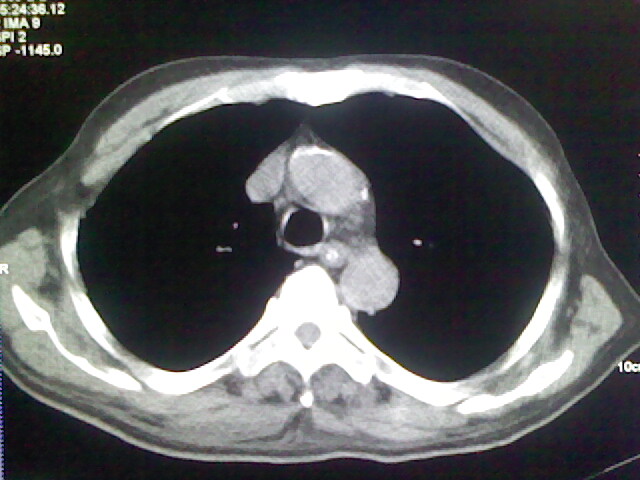

男,70岁,脑出血,长期卧床,左侧背部可触及肿块

慢性间质性炎症,与老年患者长期卧床相关,胸壁软组织及肋骨未见异常。

肺部感染,背部筋膜增厚,考虑坠积性水肿或炎症

右侧肺部见片状密度增高影,边缘模糊。考虑炎症。另食管壁增厚。